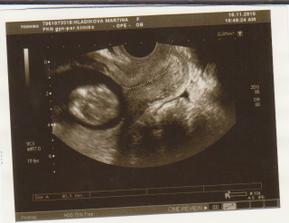

NT screening 12+4tt